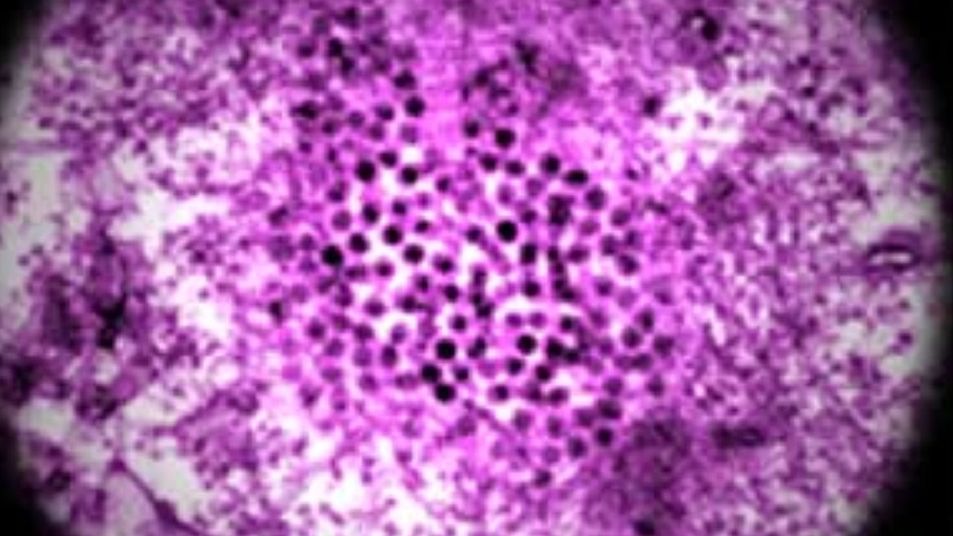

wirusWirus Zachodniego Nilu pod mikroskopem.

Źródło zdjęć: © Wikimedia Commons